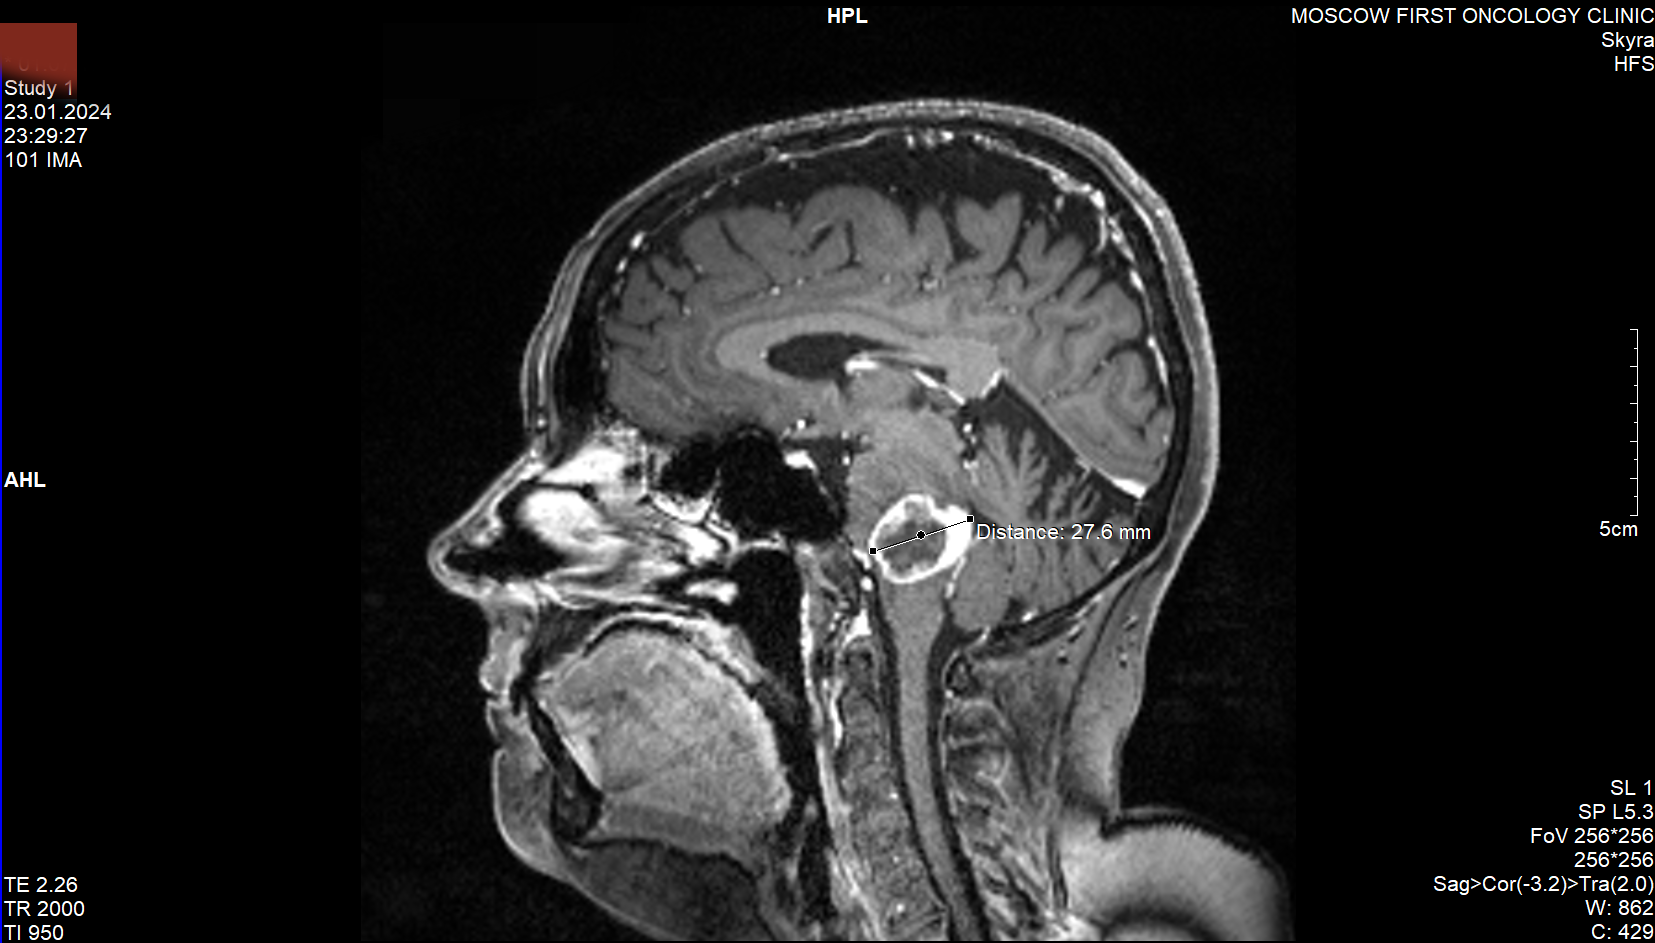

Вторая картинка - МРТ с отметкой, как я понимаю, повреждённых тканей. Удивительно, что такое большое пространство отмечено.

3,4я картинки - первое МРТ без специфических обозначений.

5,6я картинки - второе МРТ.

Как бы то ни было, заключение было следующим (текст сохранён): "По данным МРТ головного мозга с к/у от 24.01.24 пло сравнению с МРТ от 29.11.23- увеличение размеров очага в стволе головного мозга до 2, 6х2, 5х2, 4см (ранее-1.3х1.6х1.5см)... Рекомендована консультация онколога на предмет назначения лекарственной терапии (темозоломид± бевацизумаб). Врач-онколог. На предварительном заключении та-же фамилия значилась за "врач-радиотерапевт". Но это, наверное, не важно.